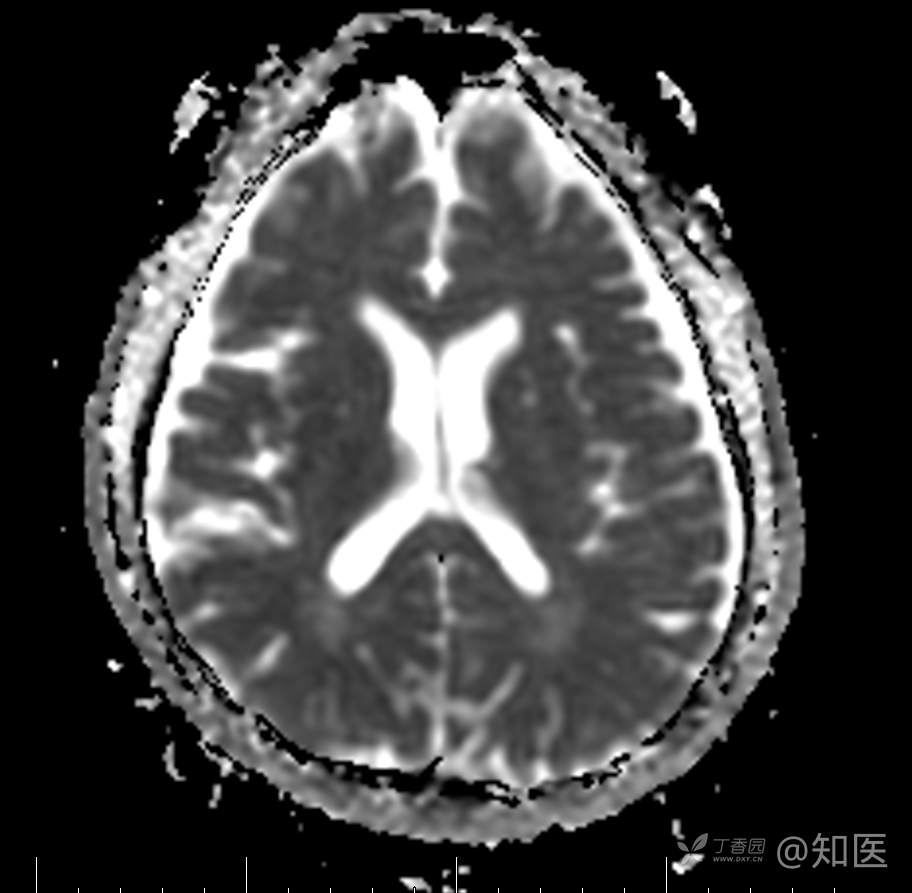

2021-6-15 ADC

2021-06-16日晨查房,患者自觉入院治疗后肢体无力症状较前稍改善,仍有活动后气短,余未诉特殊不适。ALSFRS-R评分:44分(单项均大于等于2分)。血压:123/63mmHg。神经系统查体:GCS 15分,右利手,查体合作,问答切题,粗测智能基本正常。额纹对称,双眼闭目紧,双侧瞳孔等大等圆,直径约3.0mm,对光反射灵敏,眼球运动自如,无眼震,双侧鼻唇沟对称等深,口角无歪斜。悬雍垂居中,双侧软腭抬举良好,咽反射灵敏、转颈、耸肩均一致有力。颈屈肌、颈伸肌力量5级。伸舌居中,无舌肌纤颤及萎缩。双侧岗上肌、岗下肌可见萎缩;双侧三角肌可见偶发肉跳、肌力5级,左侧肱二头肌肌力4+级、右侧4-级,双侧肱三头肌肌力4+级;双手握力可,双手大小鱼际肌及第一骨间肌可见萎缩,左侧明显,左侧手腕背伸力量4级、右侧4+级,双侧拇短展肌肌力4-级,双侧示指伸肌肌力3级,左侧指总伸肌肌力4级、右侧4-级,双侧小指展肌肌力4-级。双上肢肌张力对称减低。左侧肱二头肌反射迟钝、右侧未引出,双侧桡骨膜反射及肱三头肌反射未引出。左侧胸大肌反射阳性、右侧未引出,双侧Rossolimo征阳性、Hoffmann征阴性,下颌反射阴性。腹壁反射未引出。双下肢可见肌肉萎缩,以左侧明显;左侧髂腰肌肌力4级、右侧4-级,双侧股四头肌肌力5级,双足背伸力量3级,左足跖屈力量4级、右足4+级。双下肢肌张力对称基本正常。双侧膝腱反射、跟腱反射迟钝,双侧跖反射消失,双侧巴氏征未引出。右侧大腿外侧肌肉活检瘢痕周围浅感觉缺失,余肢体及躯干深浅感觉正常,共济运动对称正常。颈软,无抵抗,双侧布氏征及克氏征均阴性。辅助检查:微量元素(钙、镁、铁、铜、锌),微量元素测定(铅,镉)[复][2021-6-16 16:11:07]:钙1.19mmol/l;铁9.00mmol/L。急诊电解质七项[复][2021-6-16 10:41:41]:钾3.55mmol/L。血细胞分析+五分类[2021-6-16 9:57:17]:淋巴细胞百分比19.5%。[头颅,扩散成像(DWI)][头颅,磁敏感成像(SWI)][头颅,水抑制成像(FLAIR)][2021-6-16 18:10:50]:1.多发腔梗,脑白质脱髓鞘,脑萎缩。2.DWI:脑实质内未见明显高信号。3.磁敏感成像脑实质内未见明显异常信号灶。MMSE:26分(高中文化水平)。MoCA:23分。ADL评分:14分。ECAS评分:96分(ALS特异67分、ALS非特异29分)。肌电图:提示颈髓、腰髓、胸髓和延髓支配肌肉可见活动期神经源性损害,颈髓和腰髓支配肌肉同时可见慢性期神经源性损害;提示脊髓前角细胞损害可能,请结合临床。心电图大致正常。外送基因检查:TBK1基因杂合子,提示额颞叶痴呆和(或)肌萎缩性侧索硬化症4型。二线主治医师查看患者后示:1.患者基因检查结果显示TBK1基因杂合子,提示额颞叶痴呆和(或)肌萎缩侧索硬化症4型,结合外院影像学检查可见额颞叶萎缩明显,来院后复查头颅FLAIR+DWI+SWI亦提示脑萎缩,量表评估提示认知功能稍减退,ECAS评分基本正常。综上,修正诊断:肌萎缩侧索硬化症(ALS) 额颞叶变性 低钾血症 高血压2级(高危) 多发腔隙性脑梗死。因TBK1基因引起的额颞叶痴呆和(或)肌萎缩侧索硬化症为常染色体显性遗传,患者父亲已逝,母亲健在,诉无明显认知功能障碍或肌肉萎缩等表现,建议患者母亲抽血送检,进一步明确致病基因来源,必要时患者子女也可行基因检查进一步明确。2.患者目前诊断基本明确,根据文献报道,合并FTD的ALS患者整体生存周期较短(约19个月),目前患者发病已1年余,应充分与患者家属沟通病情,告知疾病预后及生存周期情况,同时建议开始口服利鲁唑片,延缓疾病进展。余治疗方案暂不予调整。密观病情变化,遵嘱执行。

2021-06-18出院总结: 卫某某,男,60岁,以“四肢僵硬1年,加重伴无力半年”之主诉入院。查体:生命体征平稳,心肺腹查体无明显异常。神经系统查体:GCS 15分,右利手,查体合作,问答切题,粗测智能基本正常。额纹对称,双眼闭目紧,双侧瞳孔等大等圆,直径约3.0mm,对光反射灵敏,眼球运动自如,无眼震,双侧鼻唇沟对称等深,口角无歪斜。悬雍垂居中,双侧软腭抬举良好,咽反射灵敏、转颈、耸肩均一致有力。颈屈肌、颈伸肌力量5级。伸舌居中,无舌肌纤颤及萎缩。左侧肱二头肌肌力4+级、右侧肱二头肌及双侧三角肌肱三头肌肌力5级;左手大小鱼际肌可见萎缩,左手握2指松、右手握力可,左手拇短展肌、示指伸肌、指总伸肌及抬腕力量3级,右手拇短展肌、示指伸肌、指总伸肌及抬腕力量4-级。双上肢肱二头肌反射、肱三头肌反射、桡骨膜反射均对称减低;双侧Hoffmann征、Rossolimo征、胸大肌反射及掌颏反射阴性,下颌反射阴性。双侧上、中、下腹壁反射可引出。左侧髂腰肌肌力4-级、右侧髂腰肌肌力4级,双侧股四头肌肌力5-级;右足背伸力量3级、左足背伸力量2级,双足跖屈力量5级。双下肢膝腱反射、跟腱反射对称减低;双侧膝阵挛、踝阵挛未引出。双侧巴氏征、Chaddock征均未引出。右侧大腿外侧肌肉活检处周围浅感觉减退,余四肢及躯干部深浅感觉正常,共济运动对称正常。颈软,无抵抗,双侧布氏征及克氏征均阴性。辅助检查:肌电图(2021-05-08,某军医大学附属医院):神经源性损害(颈段、腰骶段受累,胸段可疑;重复神经电刺激(低频、高频)可见左腋神经递减现象。 肌肉活检(2021-05-18,某军医大学附属医院):(右股四头肌)考虑神经源性损害,建议结合临床除外运动神经元病等。入院诊断:1.肢体无力:肌萎缩侧索硬化症(ALS);2.高血压1级(中危)。入院后查血清蛋白电泳:α2-球蛋白6.50%。凝血六项:血浆凝血酶原时间比值0.93;凝血酶原国际标准化比值0.93。贫血因子三项:维生素B12>1476.00pmol/L。平诊肝功十三项+平诊心肌酶谱五项+血同型半胱氨酸测定+平诊血脂八项+平诊肾功七项+平诊电解质八项:尿素3.05mmol/L;肌酐49umol/L;钾3.15mmol/L;高密度脂蛋白0.99mmol/L;载脂蛋白A1.131g/L;脂蛋白(a)333mg/L;肌酸激酶420U/L;总胆红素22.1umol/L;直接胆红素5.4umol/L。微量元素(钙、镁、铁、铜、锌),微量元素测定(铅,镉):钙1.19mmol/l;铁9.00mmol/L。急诊电解质七项:钾3.55mmol/L。血细胞分析+五分类:淋巴细胞百分比19.5%。[头颅,扩散成像(DWI)][头颅,磁敏感成像(SWI)][头颅,水抑制成像(FLAIR)]:1.多发腔梗,脑白质脱髓鞘,脑萎缩。2.DWI:脑实质内未见明显高信号。3.磁敏感成像脑实质内未见明显异常信号灶。MMSE:26分(高中文化水平)。MoCA:23分。ADL评分:14分。肌电图:提示颈髓、腰髓、胸髓和延髓支配肌肉可见活动期神经源性损害,颈髓和腰髓支配肌肉同时可见慢性期神经源性损害;提示脊髓前角细胞损害可能。血尿粪常规、免疫八项、风湿三项、血沉、传染指标、血同型半胱氨酸、糖化血红蛋白等未见明显异常。心电图、肺通气功能大致正常。住院期间给予营养神经、清除氧自由基等对症支持治疗。现患者诊断基本明确,生命体征平稳,一般情况良好,可予今日出院。出院诊断:1.肌萎缩侧索硬化症(ALS);2.额颞叶变性;3.低钾血症;4.高血压2级(高危);5.多发腔隙性脑梗死。出院医嘱:1.注意休息,加强营养,低盐、高蛋白高纤维素饮食,注意休息,适当锻炼,避免剧烈运动及重体力劳动。2.出院继续口服药物:甲钴胺 500ug/次,3次/日;辅酶Q10 10mg/次,3次/日;维生素E 100mg/次,2次/日;美金刚 10mg/次,1次/日;利鲁唑片,50mg/次,2次/日,与餐间隔1.5-2小时。3.出院继续用依达拉奉(必存)60mg+0.9%氯化钠 200ml,静滴,1次/日(首疗程14天,后每疗程10天,间隔20天,共使用6个疗程)。4.1月后门诊复查血常规、肝肾功能、电解质功能;3月后我科门诊再次复诊。5.不适随诊。